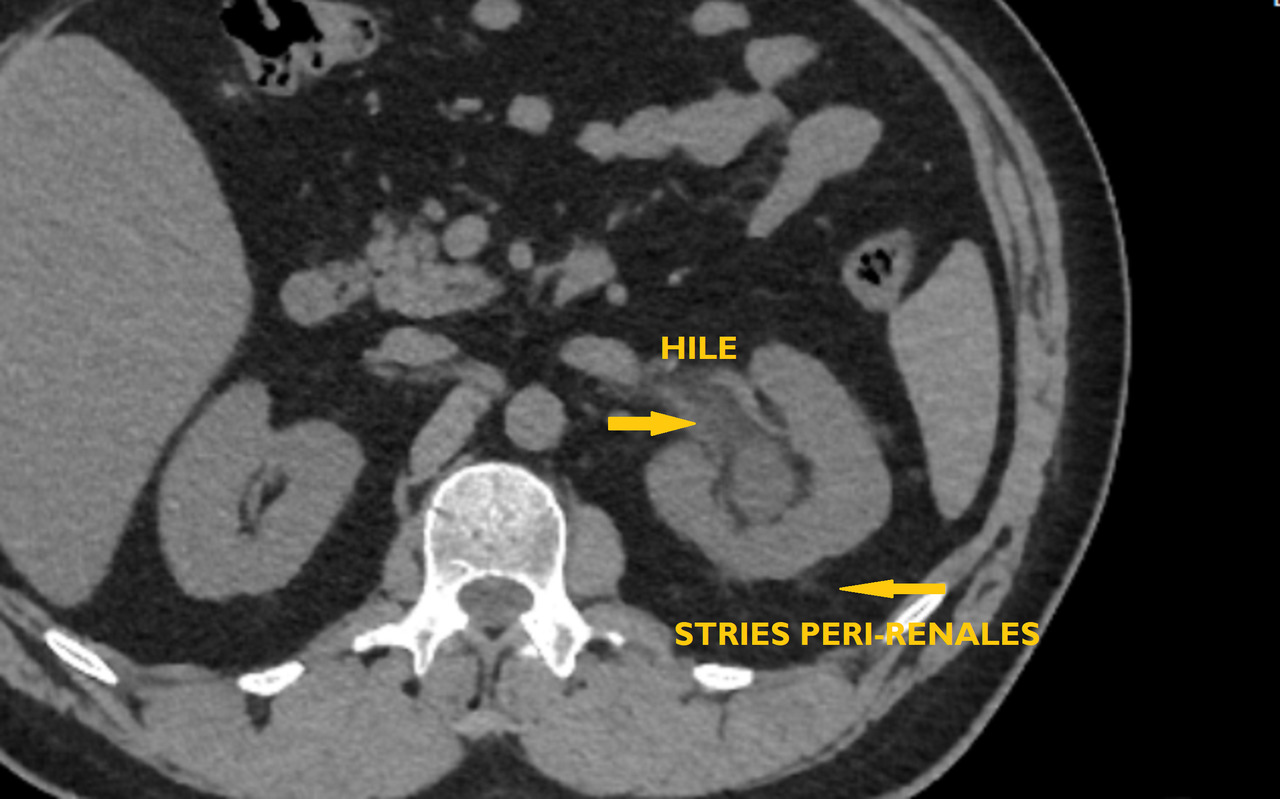

• en cas de calcul, de déterminer sa taille et sa localisation (impact pronostique important pour l’expul­sion spontanée ou le choix d’une technique interventionnelle) et leur nombre en cas de calculs multiples (fig. 1 et 2).

La sensibilité de l’échographie ou de l’abdomen sans préparation (ASP) isolément pour le diagnostic de calcul (respectivement de 80 et 90 %) ne les font recommander qu’en association (fig. 3). Pour l’imagerie initiale, cette association a été supplantée par le scanner abdominal compte tenu de sa rapidité de réalisation, pour un surcoût marginal, et de sa grande efficacité pour le diagnostic positif et différentiel. Le scanner a, en outre, un impact pronostique important pour l’expulsion spontanée (en fonction de la taille et de la localisation au diag­nostic) mais aussi le choix du traitement, la sensibilité aux ondes de choc étant à peu près corrélée à la densité tomodensitométrique.

Compte tenu du cumul d’irradiation, même de plus en plus faible grâce aux protocoles basses doses et sans injection (donc une seule hélice d’acquisition), l’examen ne peut être proposé à titre systématique itérativement pour le suivi ultérieur. En cas de doute diagnostique ou en l’absence de calcul, un complément d’imagerie avec injection de produit de contraste est recommandé.